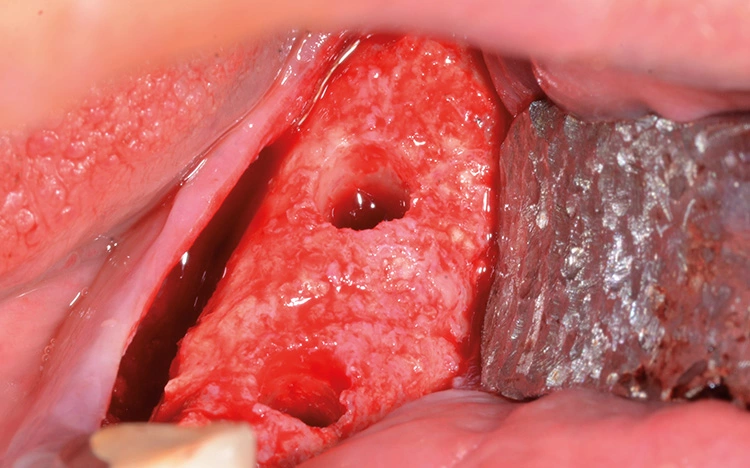

Bei der Vorstellung des Patienten zeigte sich ein qualitatives und quantitatives Knochen- und Weichgewebedefizit im linken Unterkiefer (34–37). Der Zahnverlust lag mehrere Jahre zurück und der Patient wünschte eine festsitzende Versorgung. In der radiologischen Diagnostik zeigte sich ein hochliegendes Foramen mentale.

Präoperativ wurde im Sinne eines Backward Planning erst die spätere Implantatposition und in Kenntnis dieser, die Ausdehnung des Titangitters festgelegt. Hierbei wurde festgestellt, dass sich zum einen das Foramen mentale direkt im Augmentations- und Implantationsbereich befindet und zum anderen der Verlauf des Nervus alveolaris inferior, trotz Augmentation, nur relativ kurze Implantate zulassen wird.

Bei der digitalen Planung des Gitters wurde dieser Aspekt besonders berücksichtigt und zudem auf die Lage des Foramen mentale speziell geachtet. Das Gitter wurde im Austrittsbereich ausgespart, um eine Traumatisierung zu vermeiden (Abb. 4-19).